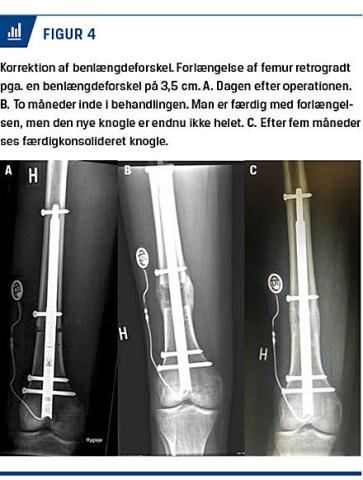

Forlængelsesmarvsøm (Figur 4) muliggør i dag skånsomme forløb [2-4], hvor intern fiksation i mange tilfælde erstatter den eksterne ringfiksator. Hermed reduceres smerter ved forlængelsen, og patienterne spares for de typiske komplikationer: infektion omkring pinhuller, skæmmende ar, fibrose m.m. samt fravær fra arbejds-, skole- og familieliv. Hos amputerede patienter med korte stumper kan der også foretages forlængelse, så de kan få bedre svingmoment i protesen [11]. Vha. forlængelsessøm kan man både forlænge, transportere og oprette skævheder, når sømmene suppleres med positionsskruer og osteotomier [12-15]. Motoriserede marvsøm drives af en ekstern elektromagnet, der driver en mindre magnet inde i sømmet, eller via induktion af strøm til en elektromotor. Når forlængelsen eller transporten er overstået, konsoliderer knoglen, mens sømmet stabiliserer.

Osteotomistedet vælges tættest muligt på deformitetens toppunkt. Distraktionen påbegyndes efter ca. fem dage med 1 mm/dag fordelt på 3-4 omgange. De første strøg af nydannet knogle er synlige på et røntgenbillede efter tre uger. Røntgenkontroller udføres regelmæssigt. Efter ti dages daglig forlængelse følger 20 dages konsolidering. Den samlede behandlingstid er derfor som tommelfingerregel en måned pr. cm, uanset om man bruger søm eller rammer. Hud, muskler, sener, blodkar og nerver udstrækkes tilsvarende og bevarer deres funktion.